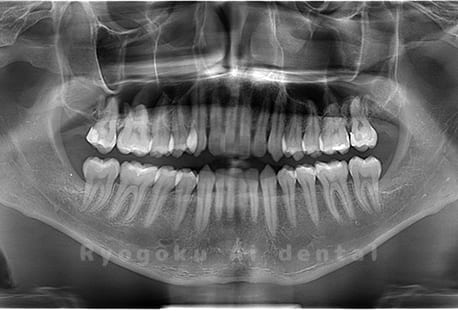

真っ直ぐ生えている親知らず

親知らずが真っ直ぐ生えているタイプです。

このタイプは真っ直ぐ生えていて咬み合わせに問題がなければ、抜歯しないケースもあります。ただし、虫歯になっていたり、痛みがあったり、咬み合わせが悪かったりすると抜歯をおすすめします。